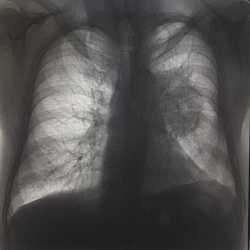

Здравствуйте. Цель исследования - исключить пневмонию. Отмечалось повышение температуры до 39, был контакт с больными, у которых пневмония была подтверждена. На мой взгляд, есть участок деформации...